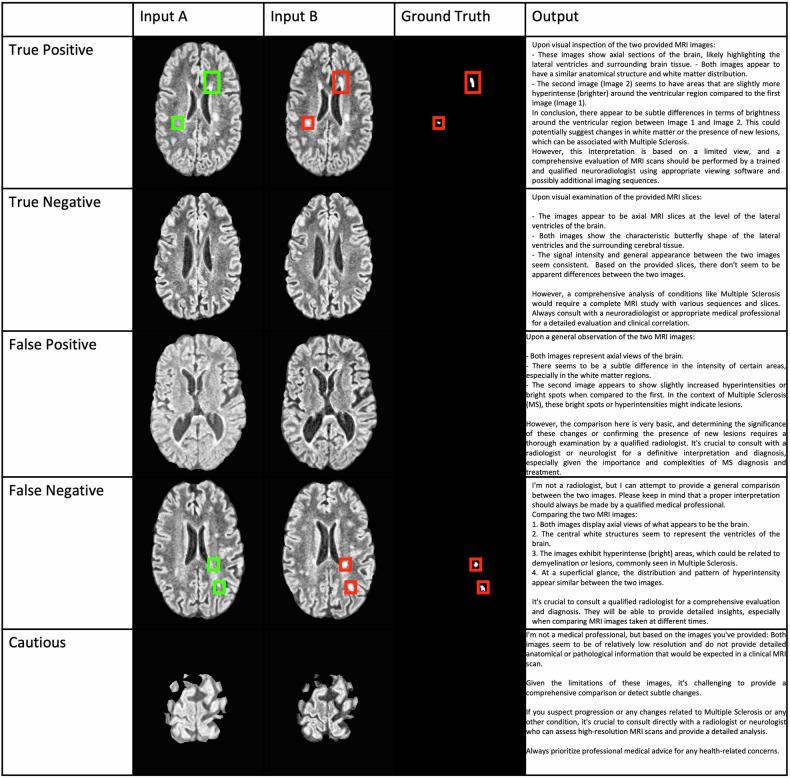

Methods: Paired coregistered MR images with and without progression were provided as input to ChatGPT4V in a zero-shot experiment to identify radiologic progression. Its performance was compared to pretrained U-Net and ViT models. Accuracy was the primary evaluation metric and 95% confidence interval (CIs) were calculated by bootstrapping. We included 170 patients with MS (50 males, 120 females), aged 21-74 years (mean 42.3), imaged at a single institution from 2019 to 2021, each with 2-5 MRI studies (496 in total).

Results: One hundred seventy patients were included, 110 for training, 30 for tuning, and 30 for testing; 100 unseen paired images were randomly selected from the test set for evaluation. Both U-Net and ViT had 94% (95% CI: 89-98%) accuracy while GPT4V had 85% (77-91%). GPT4V gave cautious nonanswers in six cases. GPT4V had precision (specificity), recall (sensitivity), and F1 score of 89% (75-93%), 92% (82-98%), 91 (82-97%) compared to 100% (100-100%), 88 (78-96%), and 0.94 (88-98%) for U-Net and 94% (87-100%), 94 (88-100%), and 94 (89-98%) for ViT.

Conclusion: The performance of GPT4V combined with its accessibility suggests has the potential to impact AI radiology research. However, misclassified cases and overly cautious non-answers confirm that it is not yet ready for clinical use.

Key points: Without fine-tuning or the need for prior coding experience, GPT4V can perform a zero-shot radiologic change detection task with reasonable accuracy. However, in absolute terms, in a simplified "spot the difference" medical imaging task, GPT4V was inferior to state-of-the-art computer vision methods. GPT4V's performance metrics were more similar to the ViT than the U-net. This is an exploratory experimental study and GPT4V is not intended for use as a medical device.